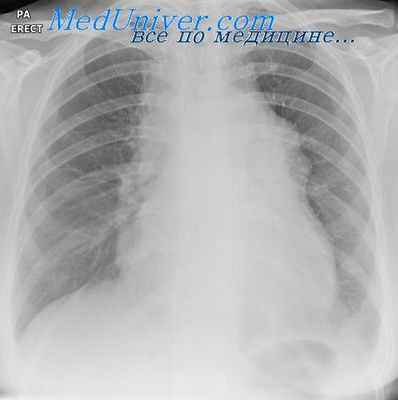

· Рентгенография органов грудной клетки.

Рентгенография грудной клетки является самым информативным методом диагностики, но назначается редко, ввиду преувеличенной опасности облучения. Лимфосаркома желез глотки диагностируется слишком поздно, так как изменение тканей неба и миндалин принимают за обычный воспалительный процесс. Заболевание периферических лимфоузлов может быть определено квалифицированным врачом при пальпации на осмотре. При наличии такого заболевания, категорически запрещено тепловое воздействие, под влияние высоких температур рост опухоли ускоряется.

План обследования больного включает: физикальный осмотр с исследованием всех групп лимфоузлов, рентгеновское исследование органов грудной клетки, УЗИ печени, селезенки, внутрибрюшных и забрюшинных лимфоузлов, фибролярингоскипию для выяснения состояния лимфоидного кольца Пирогова-Вальдейера, стернальную пункцию.